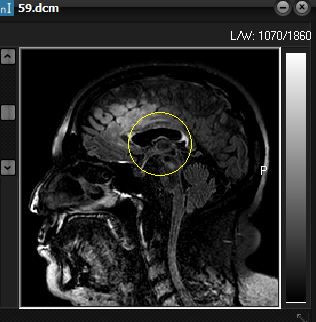

Set Centre of Gravity

By default, the centre

of gravity used to initiate the iterative search of the image volume is

automatically estimated from the input data. If the image volume includes

large non-brain regions (e.g. neck), the iteration

may not easily converge to a correct extraction of brain. This option enables

manual selection of centre of gravity region as well as the initial radius of

the search region (see figure below)

Figure 1. Setting size and position

of initial search area (‘centre of gravity’ option)